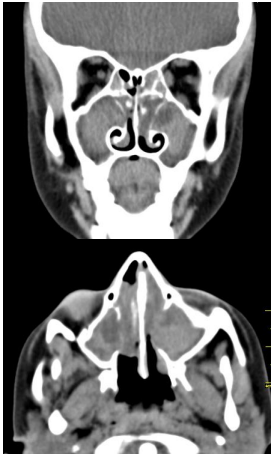

Menino, 7 anos de idade, com queixa de obstrução nasal e rinorreia posterior. Ao longo da sua vida, já foi internado por 4 vezes por pneumonias. Ao exame de endoscopia nasal, observa-se fossas nasais estreitas, pólipos nasais ocupando dois terços e secreção mucoide em ambas as fossas nasais. Imagens de tomografia dos seios da face são apresentadas a seguir:

Enunciado 4540970-1

Considerando a paciente em questão, qual dos exames abaixo confirmaria a principal hipótese diagnóstica?